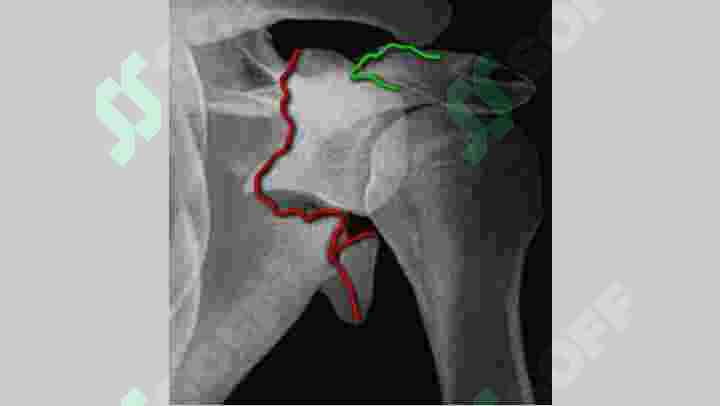

Повреждения плечевого пояса. Переломы лопатки. Переломы и вывихи ключицы. Вывих плечевой кости. Перелом проксимального конца плечевой кости.

Повреждения плечевого пояса. Переломы лопатки. Переломы и вывихи ключицы. Вывих плечевой кости. Перелом проксимального конца плечевой кости. Клиника, диагностика, лечения.

#и#с#-#s#при#по#методы#функции#конца#повреждения#плечевого#пояса.#переломы#лопатки.#вывихи#ключицы.#вывих#плечевой#кости.#перелом#проксимального#лопатки#(мкб-#42.1)#компьютерная#томограмма:#тела#сложный#многооскольчатый#нижнего#края#суставной#впадины#стабильный#нестабильный#теосинтез#флотирующая#лопатка#ключицы#фиксация#переломе#акромиального#отростка#спицами#серкляжем#нестабильность#(привычные#вывихи)#нарушения#вращательной#манжеты#плеча#(мкб#42.0)#типичный#гипсовая#повязка#полуобручем#лечение#переломов#остеосинтез#(мкб10#s43.1-43.2)#ступененобразная#деформация#надплечья#клиника#вывихов#передние#вправления#способ#мухина-мота#джанелидзе#гиппократ-купера#кости#(s#42.2)#диафиза#42.3)#дистального#42.4)#хирургической#шейки#торакобрахиальная#волковичу#скелетное#вытяжение#симптом#маркса#треугольник#линия#гюнтера#чрезмыщелковый#репозиция#чрезмыщелкового#перелома#первая#помощь#чрезмыщелковых#переломах